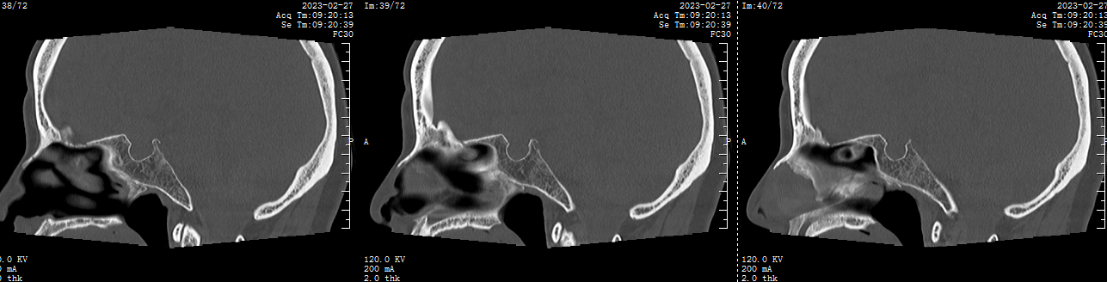

自近蝶窦前壁处向左侧推挤鼻中隔,离断筛骨垂直板,咬除部分近蝶窦处骨性鼻中隔,分离双侧鼻粘膜显露蝶窦前壁,自蝶窦开口上方做沿鼻中隔做粘膜瓣备用,末端到中鼻甲位置,将粘膜瓣压向下鼻道,高速磨钻磨除蝶窦下壁骨质,鞍结节骨质。术中视神经管清晰可见,给予保护,海绵间窦出血给予流体明胶+凝血酶止血;等离子刀一边止血一边切开硬脑膜见白色肿瘤质韧,边界清晰,大脑前动脉分支粘连于肿瘤表面,给予小心分离,以刮圈,咬切钳等小心清除肿瘤组织;内镜下将肿瘤完整切除;取右侧大腿皮下脂肪及阔筋膜备用,以人工硬膜修补和明胶海绵封闭鞍底硬膜,将脂肪放置于切口,并缝合于鞍底硬脑膜上固定铺平,阔筋膜覆盖于脂肪外边,蝶窦内充填明胶海绵止血,鼻粘膜瓣覆盖于蝶窦;碘仿纱条填塞鼻腔;护士清点棉条、器械、纱布无误,撤出鼻镜。

鞍结节脑膜瘤(tuberculumsellaemeningioma TSMs)仅占颅内脑膜瘤的4%~10%。鞍结节脑膜瘤沿脑膜向周围生长,向前可达眶尖,向后可达斜坡及小脑幕,向外沿中颅窝底扩展,向内可累及鞍内垂体腺。常最早侵犯视神经,多以视力障碍为首发症状,产生颅高压为引起头痛、恶心、呕吐,侵犯垂体会出现垂体功能障碍相应症状。